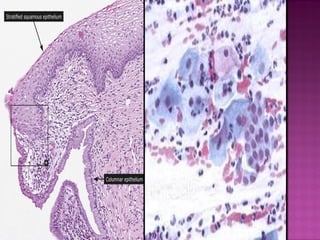

LOW GRADE SQUAMOUS

INTRAEPITHELIAL LESION

(CIN I & HPV)

 Dysplasia is an abnormal growth and

maturation of cervical squamous epithelium

 Cytological and architectural changes of

cervical cells/ loss of polarity

 limited by the basement membrane